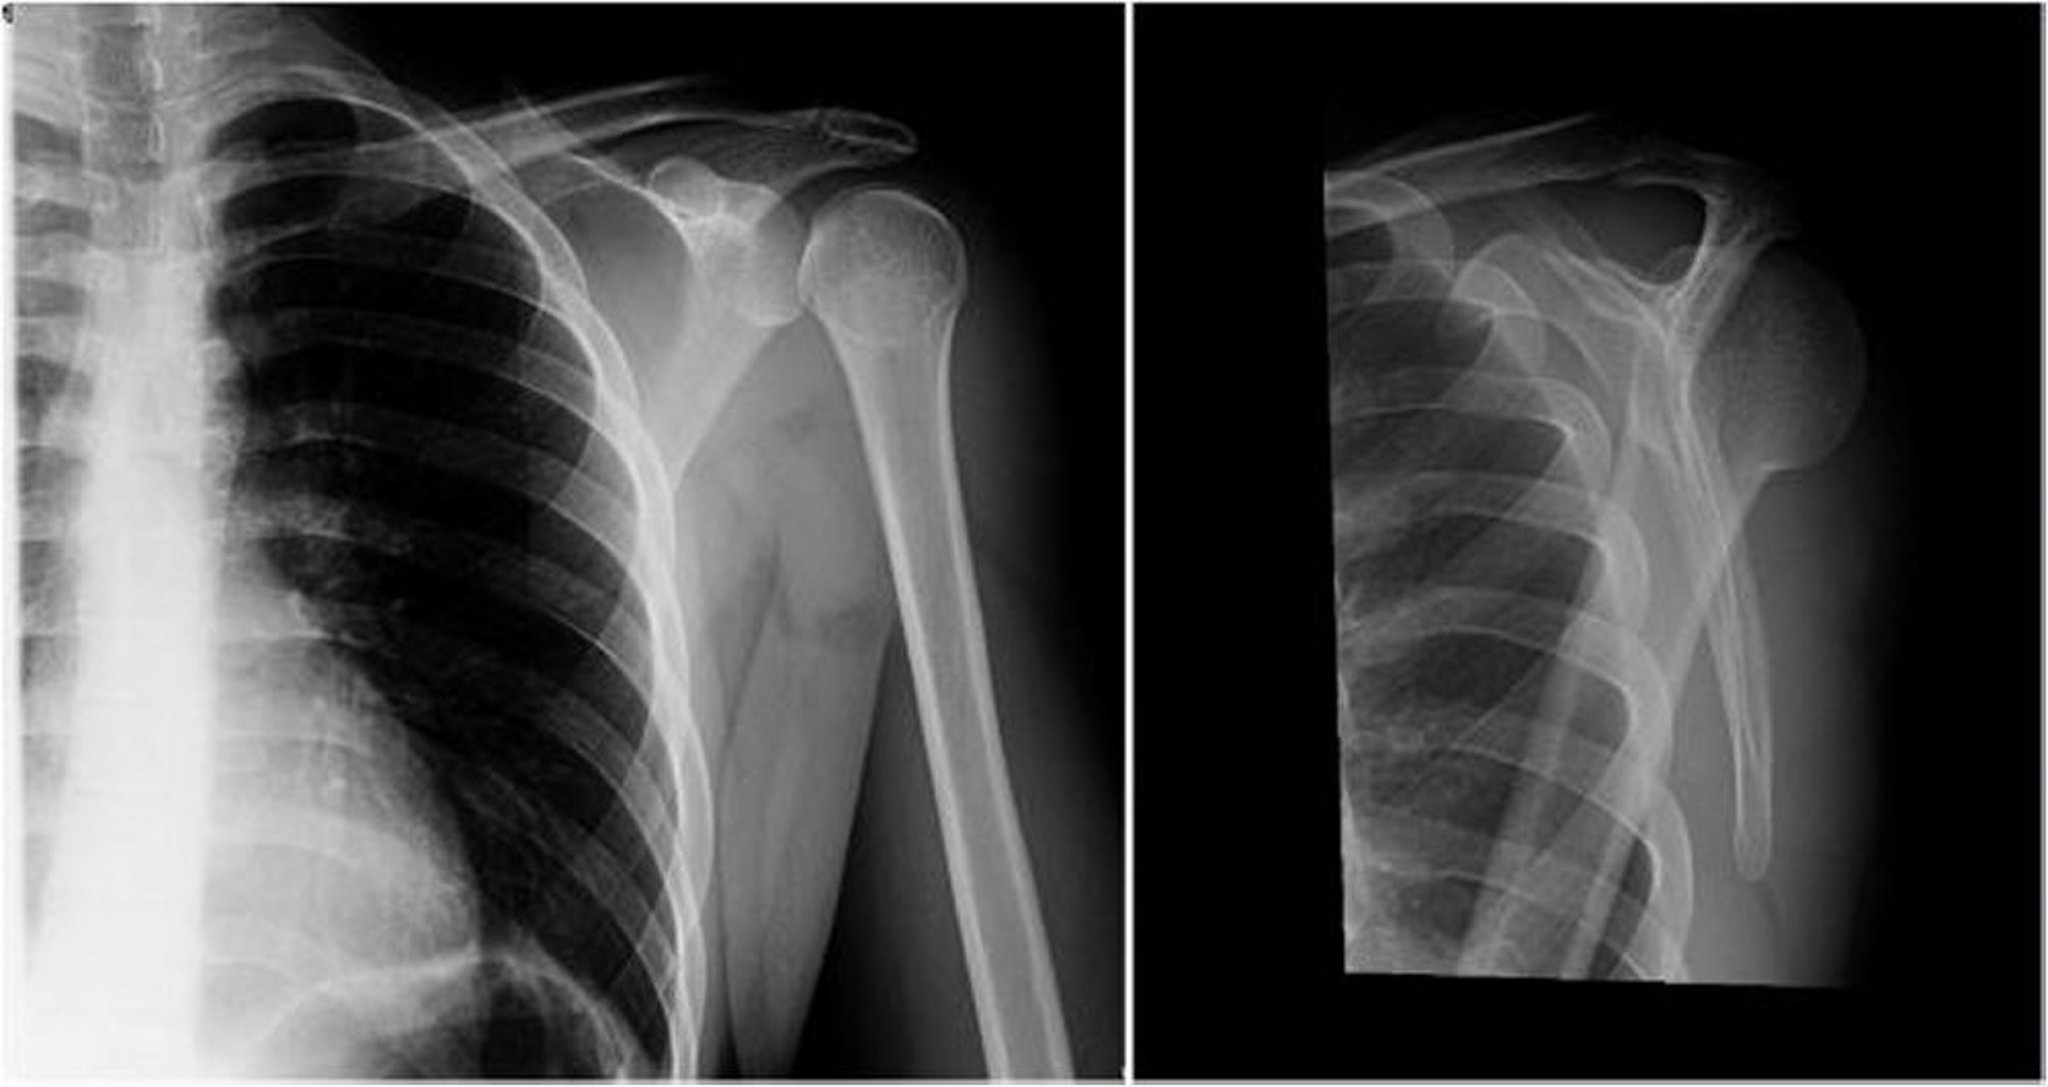

Luxation postérieure de l'épaule: vues antéropostérieures et en Y

Dans l'image de gauche (vue antéropostérieure), la tête humérale est en rotation interne, ce qui donne le signe de l'ampoule ou du cône de crème glacée (les projections des tubérosités humérales majeure et mineure ne sont pas visibles), ce qui suggère une luxation postérieure. Dans l'image de droite (vue en Y), la tête humérale est postérieure par rapport à la fosse glénoïde, ce qui montre une luxation postérieure.

Image courtoisie de Danielle Campagne, MD.